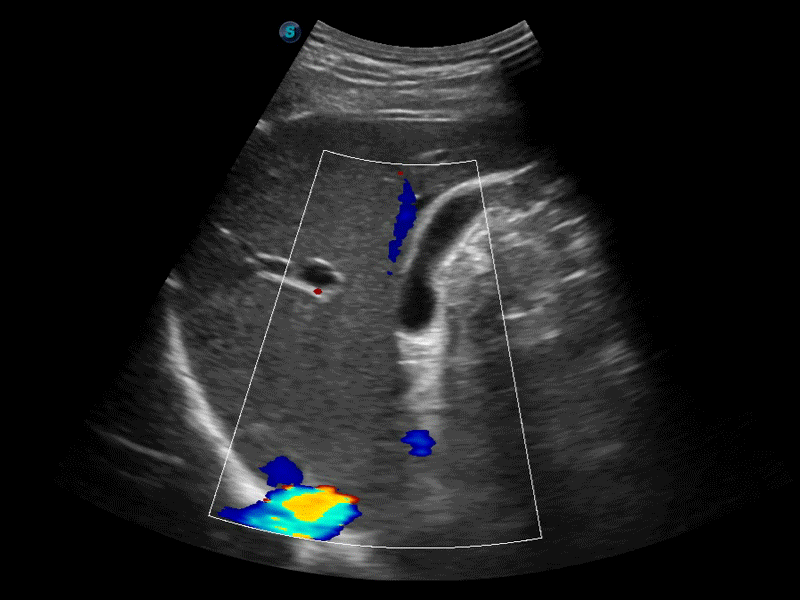

新一代微米成像技术大大提高了器官和病变的可见性。高清对比度分辨率将抑制斑点噪声,同时保持真实的组织结构。